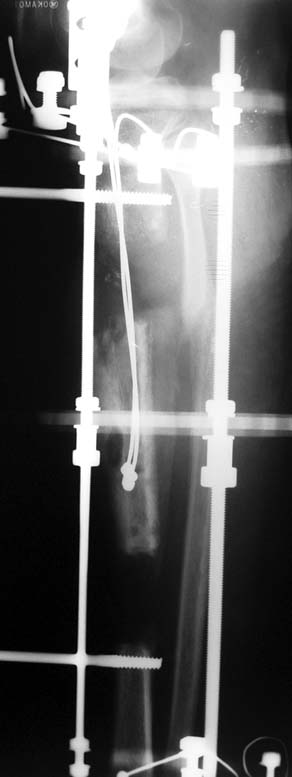

Vaka 3